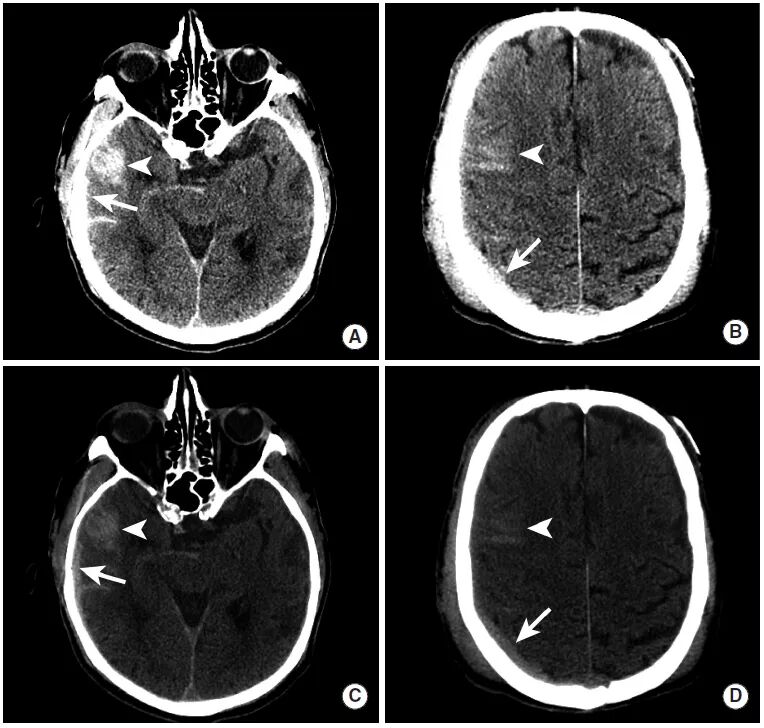

图2

交通事故后创伤性硬膜下血肿两例。

图A、B:本例患者于

图C、D:本例患者接受影像学检查时处于反应迟钝状态。平扫CT可见巨大的双凸面形硬膜外血肿(长尾箭头),并可见显著占位效应,导致左侧中线移位和大脑镰下疝(三角箭头),以及小脑幕切迹疝(虚线箭头)。